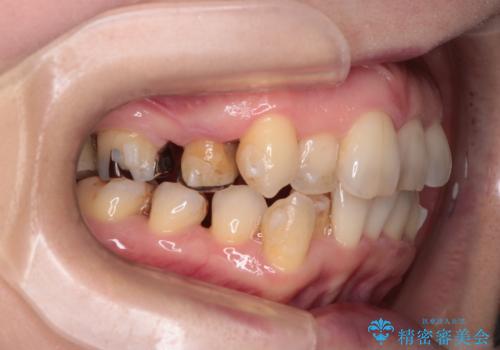

- 右上の八重歯(犬歯の突出)と、それに伴う歯並びのがたつきを主訴にご来院されました。精密検査の結果、八重歯を正しい位置に収めるためのスペースが大幅に不足していることが分かりました。

通常、矯正治療では4番目の歯を抜歯することが多いですが、今回は歯の状態や全体の噛み合わせのバランスを考慮し、右上5番(第二小臼歯)を抜歯してスペースを確保する計画を立案。装置には、周囲に気づかれずに治療を進めたいというご希望に合わせて、透明なマウスピース型のインビザラインを採用しました。

今回の治療では、右上5番の抜歯スペースを活用して八重歯(3番)を後方へ誘導しました。